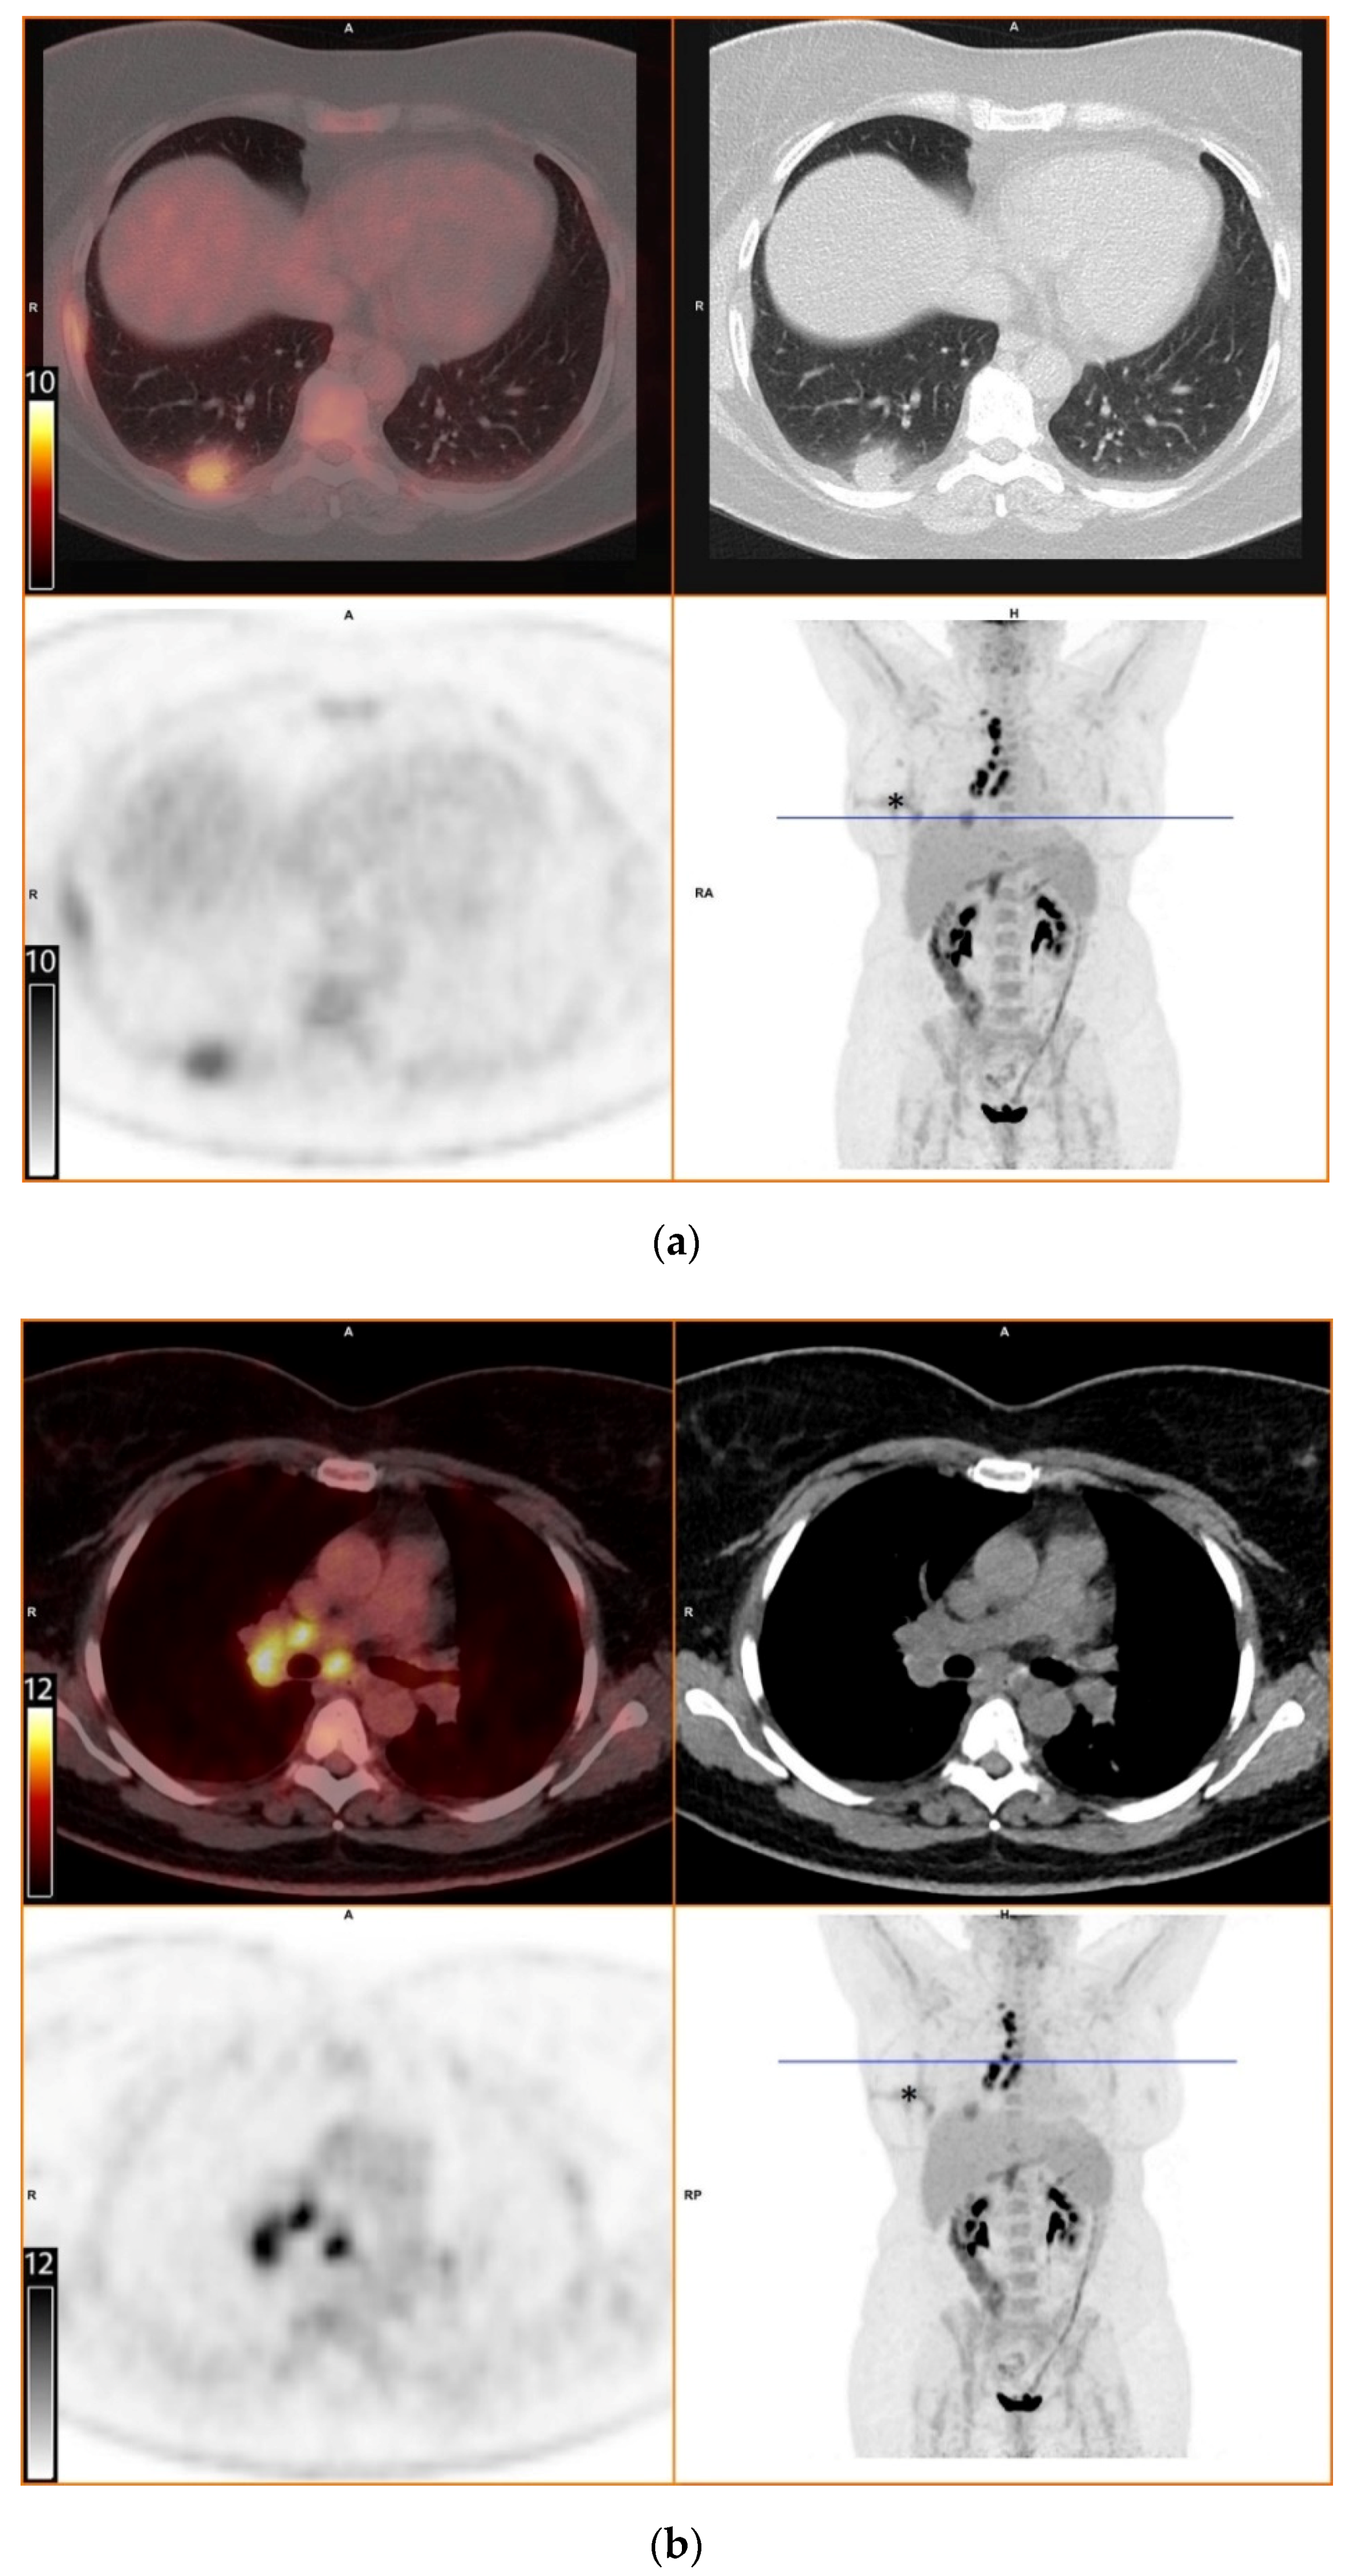

To further evaluate the suspected malignant disease, a [18F]FDG-PET/CT was performed (day +14). It detected multiple hypermetabolic lymph nodes of up to 33 mm in diameter, located right interlobar, at the right hilus, the mediastinum and right supraclavicular. The previously known lesion of the right lung showed only moderate metabolic activity. In addition, a moderately active precaval lymph node was detected (Figure 1).

Figure 1.

[18F]FDG-PET/CT. Upper left: PET and CT fusion images. Upper right: CT images. Lower left: PET images. Lower right: Maximum intensity projection. Blue line: Axial imaging level. Scale bars: Standardized uptake value. Star: Postinterventional diffuse uptake of the right thoracic wall after chest tube placement. (a) Moderate uptake in a solitary solid pulmonary lesion with irregular margins in the right lower lobe of the lung (b) Greater uptake in the draining lymph nodes right interlobar, right hilar and mediastinal (c) A further draining right supraclavicular lymph node showing high uptake as well (d) Moderate uptake in a precaval abdominal lymph node.

The diagnostic contribution of [18F]FDG-PET/CT has been demonstrated in invasive fungal infections, especially in detecting occult foci. [18F]FDG-PET/CT is capable of detecting increased metabolic activity, indicative of inflammatory cell activity, prior to the onset of anatomical abnormalities detectable by conventional radiological means. However, discriminating infection from malignancy and other inflammatory diseases remains difficult [12,13,14]. In our patient, [18F]FDG-PET/CT revealed intense metabolic activity in intrathoracic and supraclavicular lymph nodes. In contrast, the pulmonary lesion in the right lobe displayed only moderate metabolic activity. This finding of equal or greater FDG uptake in draining lymph node(s) in comparison with the associated lung nodule was described by Nagelschneider as “flip-flop fungus sign” (Table 1) with a sensitivity of 60% and specificity of 85% for benign fungal disease, predominately histoplasmosis in a study population from an endemic area [2]. Another approach by Kadaria suggested that dual time point [18F]FDG-PET/CT can be a helpful diagnostic tool for discriminating between benign and malignant lesions in areas endemic for H. capsulatum [15]. The latter radiologic technique was not used in our case. Although useful, [18F]FDG-PET/CT is not recommended in routine diagnostics of fungal infections, mainly due to high costs and generally low availability.

In our opinion, some aspects of the present case need to be addressed explicitly. First, the precaval lymph node with moderately elevated FDG uptake and the concomitant hepatitis remain unexplained but, in retrospect, could be attributed to hepatic involvement in histoplasmosis, which may occur in immunocompetent patients on rare occasions [16]. Second, the negative serological and molecular markers in our patient may be explained by the delay in diagnosis to a time when the infection was already resolving, the poor sensitivity of these tests in non-disseminated disease and the intermittent immunosuppressive therapy with corticosteroids. Third, the initial histopathologic evaluation of the resected lymph nodes with Ziehl-Neelsen, PAS and Giemsa stains revealed necrotic granuloma but failed to identify a fungal pathogen. Although certain phases of H. capsulatum can be visualized by these stains, silver stains, such as Grocott’s methenamine silver stain, are considered the most reliable for the detection of H. capsulatum [7,17,18]. Of note, silver stains may be falsely negative in cases with very few fungal organisms. Fourth, the absence of fungal organisms in the primary CT-guided core needle biopsy of the pulmonary lesion was most likely due to a sampling error. The finding of organizing pneumonia in the biopsy, which often surrounds necrotic lesions, supports this assumption.

Overall, this case stresses the importance of obtaining a careful travel history in a country where histoplasmosis is extremely rare and radiological findings can be mistaken for more common disorders, like malignant or autoimmune diseases. It also highlights the importance of knowledge about possible imported infectious diseases for effective diagnostics. With this case report, we also add further images to the limited database on [18F]FDG-PET/CT findings in patients with histoplasmosis and illustrate the potential diagnostic value of the “flip-flop fungus sign”.